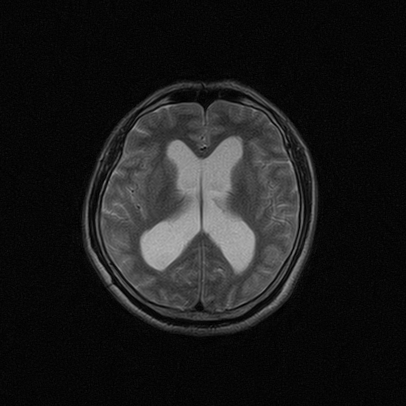

标题: MRI2064:少见病例。男性52,视力下降多年。 [打印本页]

标题: MRI2064:少见病例。男性52,视力下降多年。

四脑室区见混杂信号占位影,脑室系统扩张明显,临近结构显著受压称位,患者52岁,多考虑室管膜瘤可能性大

考虑第四脑室室管膜瘤并阻塞性脑积水。

考虑第四脑室室管膜瘤并梗阻性脑积水;部分性空蝶鞍;左侧上颌窦粘膜下囊肿。

考虑第四脑室室管膜瘤【血供丰富血管母细胞瘤可能】并梗阻性脑积水;部分性空蝶鞍;左侧上颌窦粘膜下囊肿。

比较典型的脉络丛乳头状瘤并脑积水,鉴别小脑蚓部血管母细胞瘤。